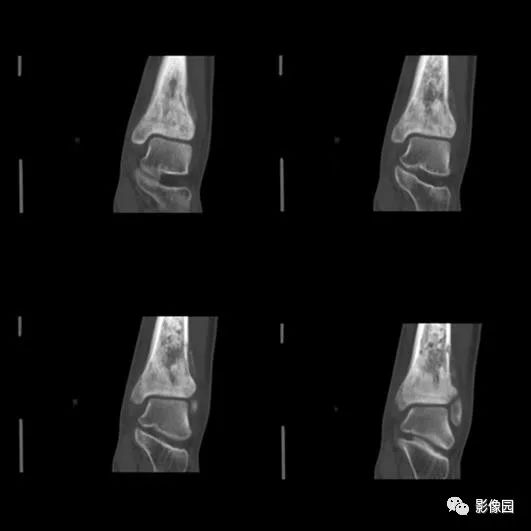

2016-05-11复查

评论:前片X线示左胫骨下段及干骺端病变,髓腔内密度不均匀增高,内侧骨皮质可见骨质破坏,可见骨膜反应。CT示病灶内见多发斑片状肿瘤骨(黄色箭头),周围可见针状骨膜反应(红色箭头)。周围软组织肿胀。MRI示胫骨下段以长T1、长2信号为主的混杂信号影,未跨越胫距关节面,周围未见明显软组织肿块。周围软组织广泛片状长T1长T2信号影。复查X线示病变较前片明显进展,左侧胫骨远段及干骺端骨质破坏,周围可见针状骨膜反应及Codman三角(蓝色箭头)形成。相邻左侧腓骨下端、距骨滑车受累。

骨膜新生骨和Codman三角:是骨肉瘤常见而重要的表现,但不具有特异性。